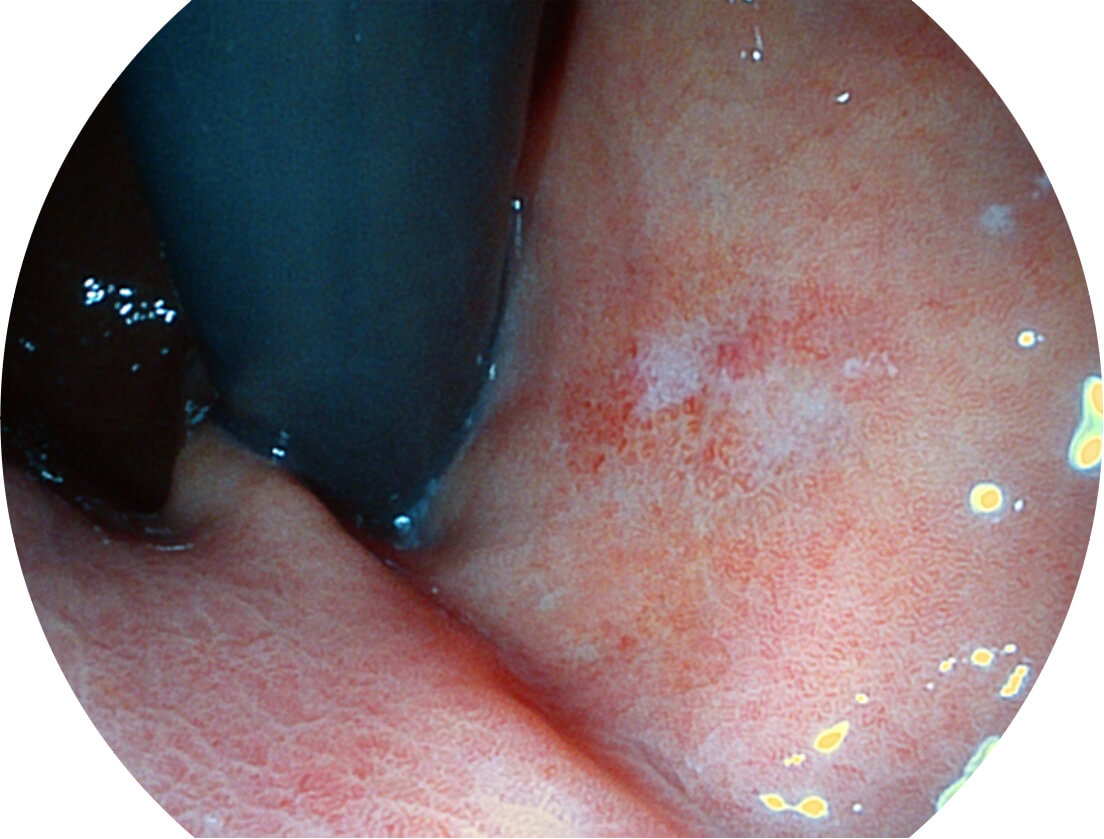

强调浅层黏膜结构的同时,保证照明亮度和提升浅层微血管与中层血管颜色对比度,病变边界更清晰。

采用光路合束技术,光谱自由度高,实现了更丰富的照明模式,染色模式SFI及VIST,从远景到近景,助力消化道早期疾病诊断。

送水方向与手术器械方向,两者更贴合,能快速冲洗黏膜表面的粘液及出血,发现病变和出血点。